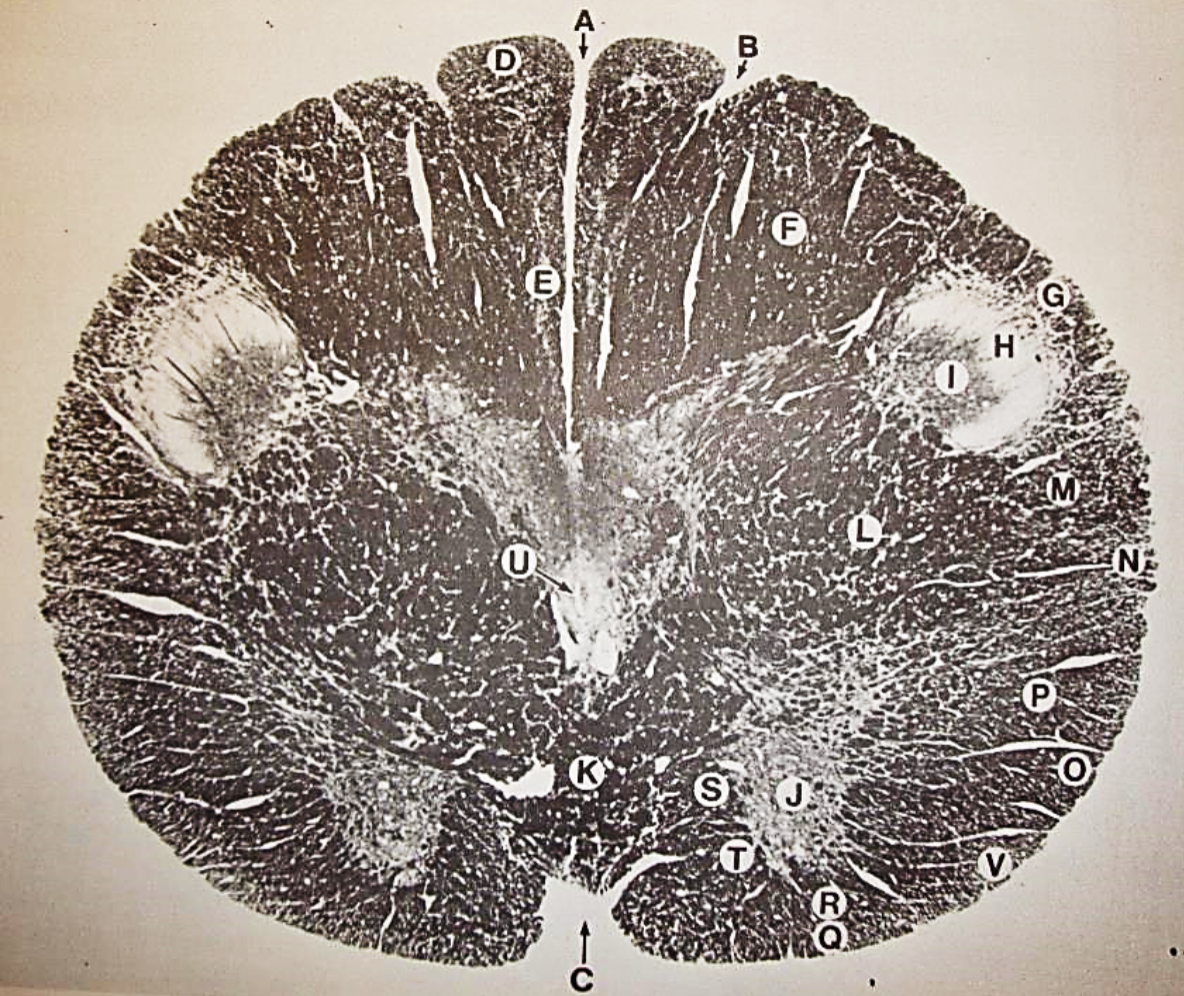

A

Lateral Cuneate nucleus

B

dorsal external arcuate fibers

C + D collectively

vestibular nuclei

C + D collectively

vestibular nuclei

E

dorsal motor nucleus of vagus nerve

F

solitary fasciculus

G

solitary nucleus

H

nucleus ambiguous

I

fascicles of glossopharyngeal nerve

J

hypoglossal nucleus

K

fascicles of hypoglossal nerve

L

dorsal longitudinal fasciculus

M

central tegmental tract

N

inferior olivary nucleus

R

inferior cerebellar peduncle

S

spinal trigeminal tract

T

spinal trigeminal nucleus

U

ventral trigeminothalamic tract

V

pyramidal (corticospinal) tract

W

rubrospinal tract

X

anterior spinocerebellar tract

Y

spinal lemniscus

Z

medial longitudinal fasciculus

a

tectospinal tract

b

medial lemniscus

c

vagus nerve

d

inferior salivatory nucleus